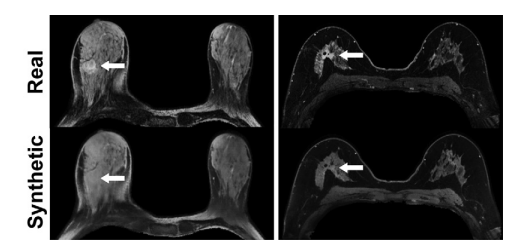

_Figure 5: MRI scans in a 55-year-old woman with right invasive ductal carcinoma (left panel)_and a 67-year-old woman with right invasive ductal carcinoma (right panel) show failed enhance ment of the index lesion (arrow) on the simulated (ie, synthetic) contrast-enhanced MRI scans.

图5: 一位55岁女性(左侧面板)和一位67岁女性(右侧面板)的右侧侵袭性导管癌MRI扫描显示,在模拟(即合成)的对比增强MRI扫描中指数病灶(箭头)未显示增强。